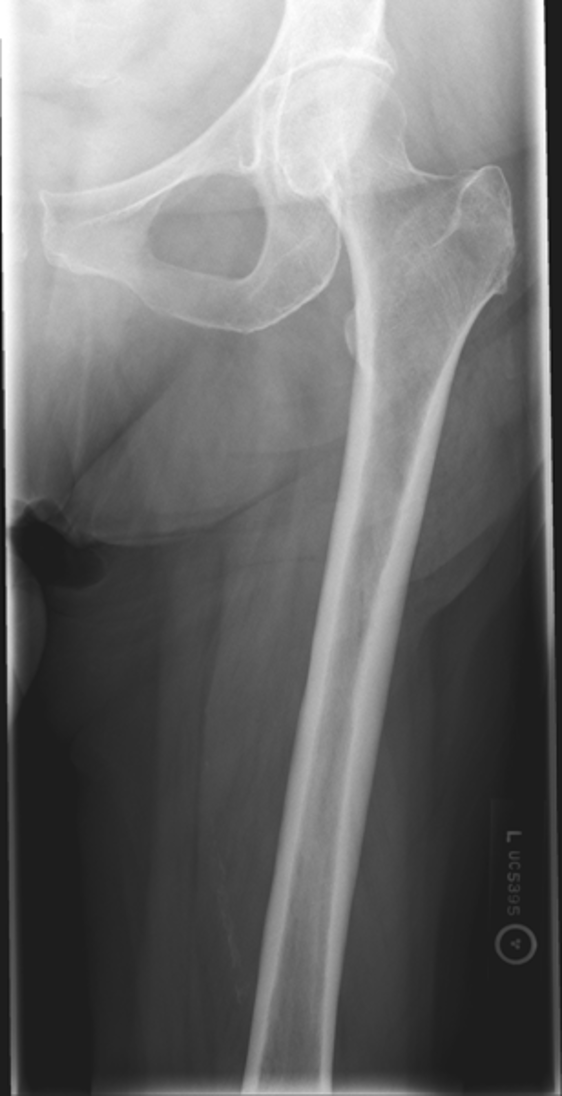

lesser trochanter not seen beyond the medial border of the femur

only very small portion

what is the main critique for an AP femur?

under rotated

what is the image critique of this AP femur?

good image